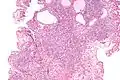

Nephrogenic adenomas are diagnosed under the microscope by pathologists. Microscopically the tumor shows closely packed small tubular structures in edematous stroma. The tubules show considerable variation in size and shape resembling convoluted tubules of the kidney. The single layer of cells lining the tubules are cuboidal with a scant to moderate amount of cytoplasm. In some areas they may have a hobnail appearance. [2]

Low mag -

High mag